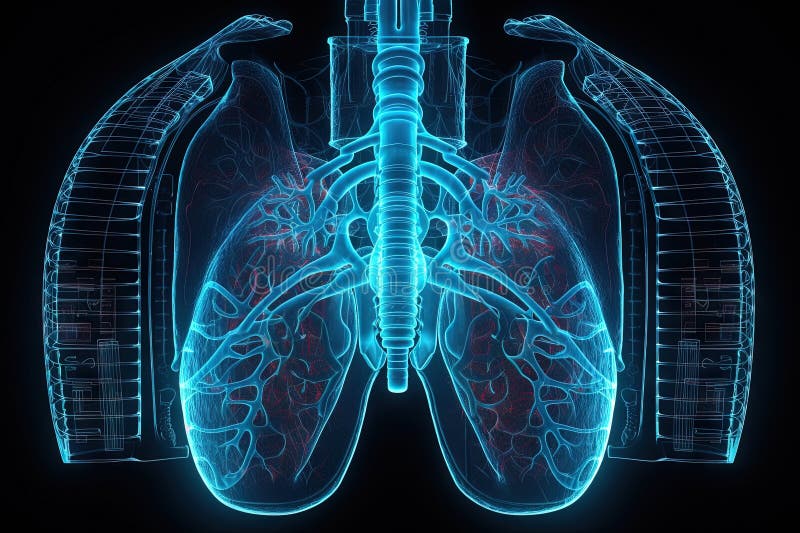

Artificial implant science concept with technological AI lungs on the circuit board. Generated AI AI generated